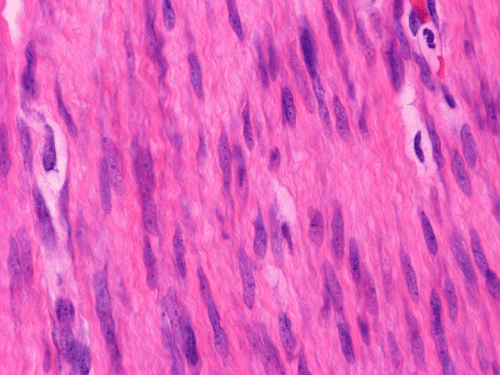

The excised mass is composed of an intermingled arrangement of mature adipose tissue, densely packed primitive spindle cells with small amount of cytoplasm, and mature appearing spindle cells with substantial amount of cytoplasm that gives the appearance of smooth muscle (Panel  A). Abrupt transition between the three elements are common (Panel B). The densely packed, small primitive spindle cells have elongated, cigar-shaped nuclei with amphophilic cytoplasm. Pleomorphism and mitotic figures are not seen. A small number of lymphocytes are present among these cells (Panel C). In areas with appeance of smooth muscle, the cells have elongated, sometime wavy nuclei without significant pleomorphism or mitosis (Panel D). Areas with thick, wavy collagen fibers admixed with benign appearing spindle cells are also present (Panel E and F) and some of these areas are more loosely packed than the other areas which may mimic the appearance of a neurofibroma. In contrast to other areas, these collagenous areas merge imperceptibly with the more cellular areas. In some of the densely packed spindle cell areas, there are small packets of loosely packed cells that give a myxomatous morphology on high magnification (Panel G and H).